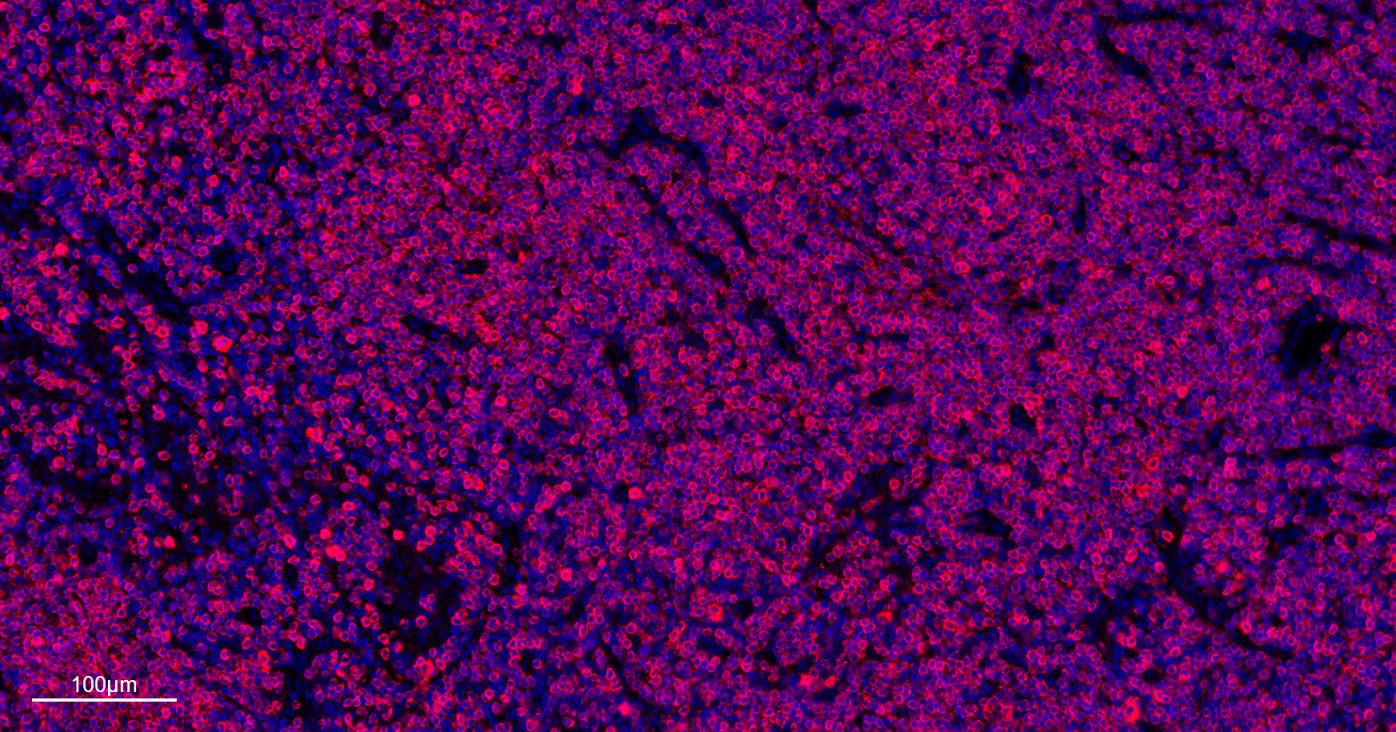

IFHuman, Mouse, Rat1:500-2000